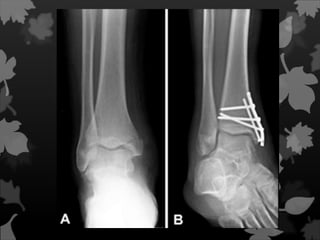

Fraturas de Smith e

Colles

Fratura que acomete a parte

distal do rádio.

Fraturas de Smithe Colles Fratura que acomete a parte distal do rádio.